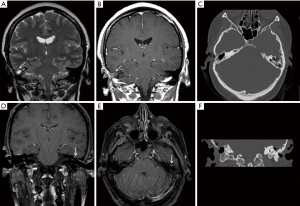

High resolution CT (HRCT) of the temporal bones was performed, demonstrating soft tissue opacification in the attic and sinus tympani. There was also a suggestion of a tegmen defect. MRI of temporal bones demonstrated a small (5 mm) mass in the epitympanum separate from the tegmen tympani defect. This lesion showed no restricted diffusion and was isointense to adjacent temporal cortex on T1 and T2 weighted images. Peripheral enhancement was seen on post contrast images (Figure 1).

In general, our series of MRI images of the lesions showed no restricted diffusion and isointensity to adjacent tissue on T1 and T2 weighted images (Figure 1). Similar features have also been described by Wu et al. (12) and Rizk et al. (13).

A tegmen defect was present in all cases and glial choristomas were either adherent to the tegmen tympani or ossicular chain but were separate from the tegmen defect by 10–12 mm (Figure 2). There was no herniation of meninges nor brain tissue. A CSF leak was encountered in two of the cases (cases 3 and 4) in the process of removing granulations from around the choristomas. No patients developed any CSF leaks prior to surgery.